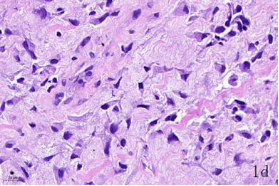

NDN(Necdin)屬于黑色素瘤抗原(MAGE)家族,由60多個基因構(gòu)成共享高度保守的MAGE同源結(jié)構(gòu)域(MHD)[6,7]。最近幾年的研究提出NDN是一種新的抑癌基因,其在卵巢癌[8]、乳腺癌[9]和黑色素瘤[10]等的組織和細胞系中低表達,過表達NDN可以抑制其生長,但NDN在骨肉瘤中的作用及機制尚不清楚。為探討NDN在骨肉瘤中的作用及途徑,我們收集了骨肉瘤患者的石蠟標本以及臨床信息,對其進行了免疫組化檢測及生存分析。通過對骨組織和骨肉瘤HE染色發(fā)現(xiàn),骨組織組,骨密質(zhì)呈板層狀,陷窩中可見骨細胞呈梭形排列( 圖1 a 1b) ;骨肉瘤組,瘤細胞呈多角形,核大深染,核分裂多見,瘤細胞呈車輻狀排列,瘤細胞間可見少量腫瘤性骨質(zhì)形成(圖1c1d)。同時通過免疫組化發(fā)現(xiàn),NDN表達主要位于細胞的胞核中。NDN在骨肉瘤組織中的表達率為29.4%(15/51)(圖1c1d),明顯低于瘤旁骨組織陽性表達率80%(8/10)(圖1a1b)。